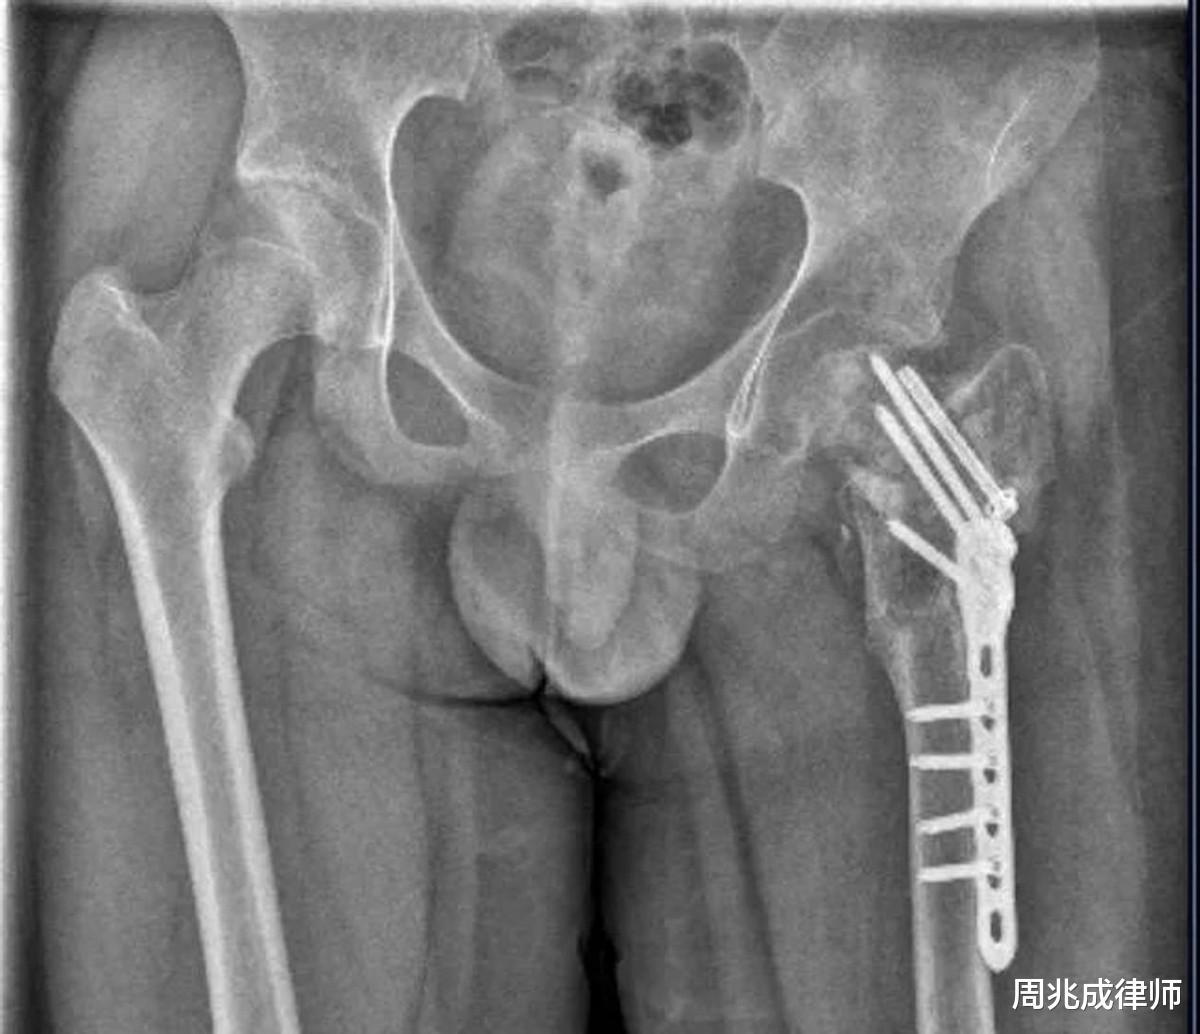

虐待被监护、看护人罪,是指对未成年人、老年人等负有监护看护职责的人员,虐待被监护看护的人。而本案中,校长向某胜、教官与小武之间的关系就是因教育形成的看护关系,其通宵罚站、关小黑屋、跪举水盆等持续虐待行为,符合该罪的构成要件,且针对未成年人属法定加重情节。而且,小武左髋部重伤二级需植入钢针钢板,伤情是骨折后遭反复踢踹、延误治疗导致,已超出虐待的范畴,构成独立的故意伤害罪。校长向某胜作为主谋,对骨折后仍施暴的行为负主要责任,所以被数罪并罚,而3名教官未参与重伤级伤害,仅以虐待被监护、看护人罪起诉。两罪的区分关键在于虐待罪侧重持续性、经常性的精神与肉体折磨,故意伤害罪侧重单次或多次叠加造成的明确伤害后果,本案中两种行为独立存在且均达定罪标准,所以需分别评价后数罪并罚。

先看校长向某胜两罪并罚,虐待被监护、看护人罪最高刑期3年,故意伤害罪重伤二级对应的量刑区间为3-10年,结合他冒充公益组织办学、持续虐待28天、骨折后仍施暴、拒绝及时救治等加重情节,最终刑期会在3年以上。那3名教官呢?他们作为直接施暴者,虽未涉故意伤害罪,但参与全程虐待,且机构无资质、针对未成年人作案,量刑将向3年法定上限靠拢。值得注意的是,现行《刑法》中虐待被监护、看护人罪最高刑期仅3年,与“重伤二级”的严重后果存在适配差距,这也是舆论呼吁增设虐童罪的原因。